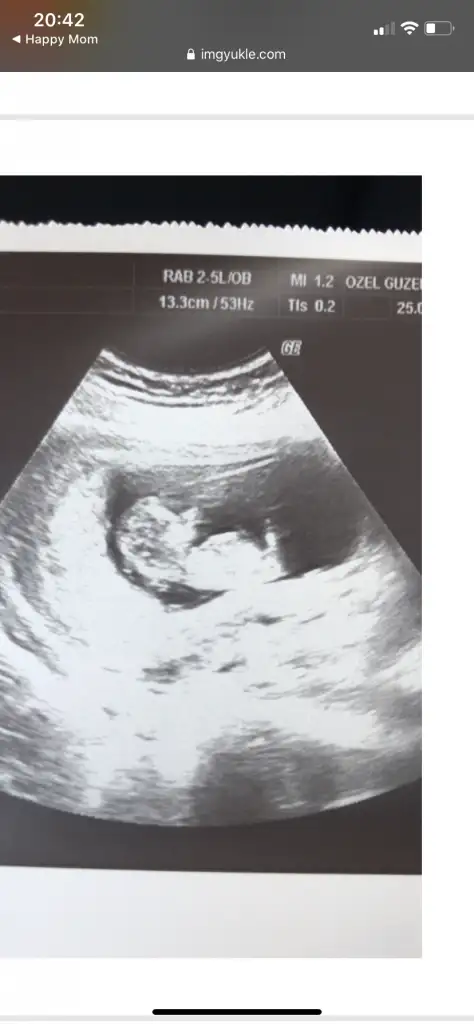

Cnm 11 12 13 hafta olmalı usg netdeğil eminde olamadım şimdilik erkek sanki tekrar usg bekliyorumTahmin yapabilir misin canım ?

Kız sanki başka usg varsa paylaşın emin olamadım12 haftalik cinsiyet nedir sizce :)

Pozisyonu değiştirmiyorsa hani popo yukarı dogru nubu çok dik gelmedi bana şimdilik kız ama emin değilim başka usg varmıIkra meyra Canım tahmin yaparmısın???

Bu haftaya kadar erkek dedin canım nubda kız diyorsan kızdır ozaman nasip doktorda emin değilim ama kıza benziyor dedi 3. Kızımız gelecek bu durumdaPozisyonu değiştirmiyorsa hani popo yukarı dogru nubu çok dik gelmedi bana şimdilik kız ama emin değilim başka usg varmı